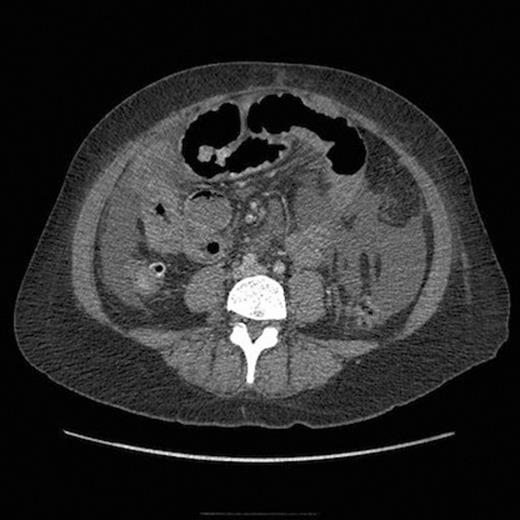

A week later the patient required emergency admission with a three day history of generalised abdominal pain and vomiting. An initial abdominal radiograph was suggestive of small bowel obstruction. However, computerised tomography revealed extensive small bowel wall thickening and ascites without evidence of mechanical obstruction or viscus perforation (figure 2). In addition, the C-reactive protein (CRP) and urea were elevated with a raised urine protein/creatinine ratio suggestive of nephritis. Overnight the patient deteriorated rapidly developing peritonitis and septic shock. Following a bolus dose of intravenous methylprednisolone, an emergency laparotomy revealed turbid ascites and patchy ischaemia throughout the entire small bowel with a perforation 150 centimetres from the duodenojejunal flexure. The perforated segment was excised and a defunctioning ileostomy and mucous fistula was formed. Post-operatively, the patient was admitted to the intensive care unit for multi-organ support and commenced on a course of intravenous methylprednisolone with two cycles of intravenous cyclophosphamide.